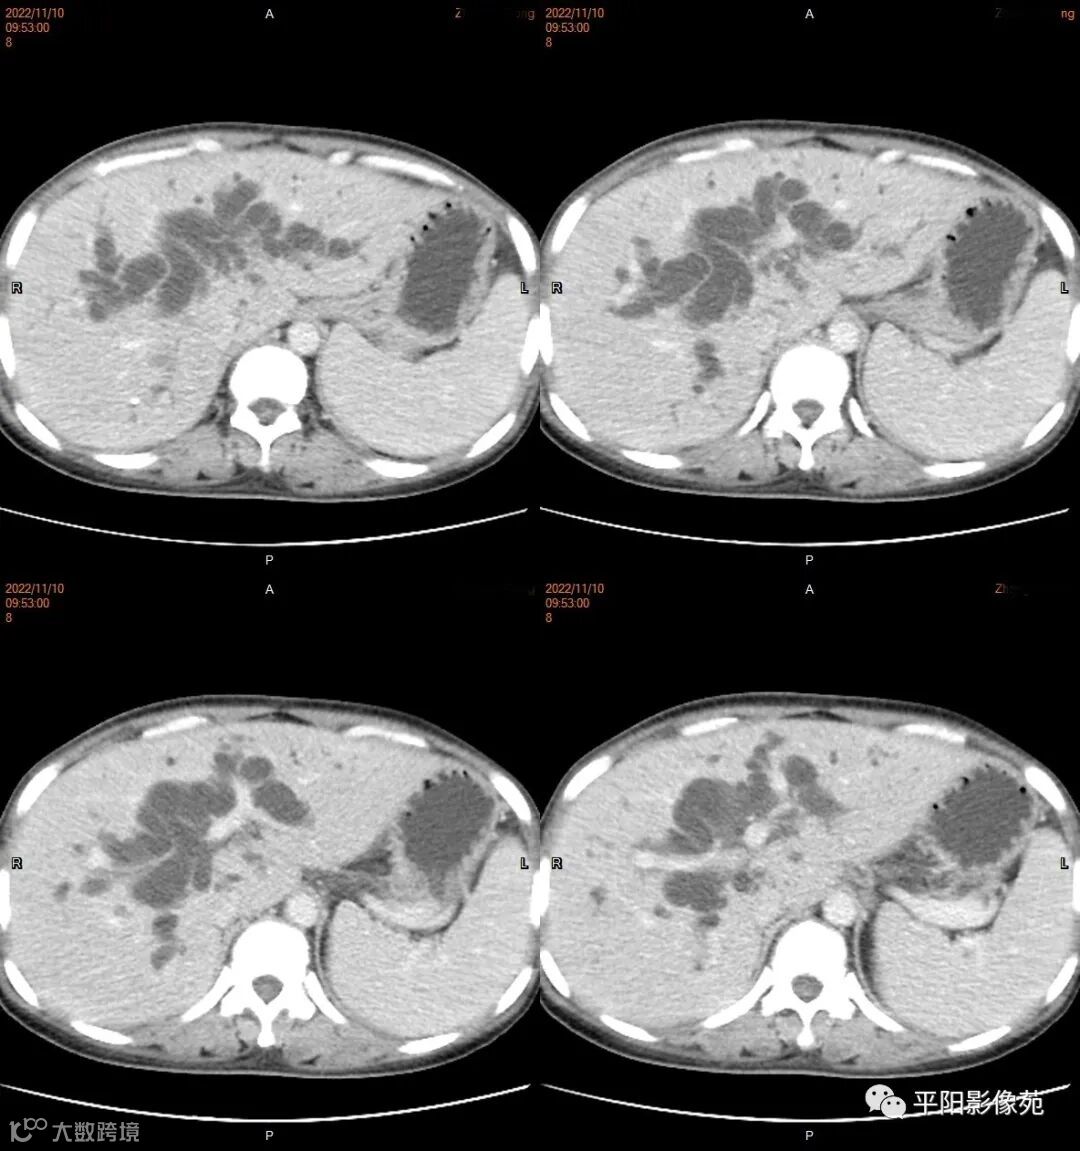

影像学检查

CT

肿瘤病理基础以肉眼形态分型可分为息肉型、溃疡型、缩窄型、弥漫狭窄型。

影像表现: